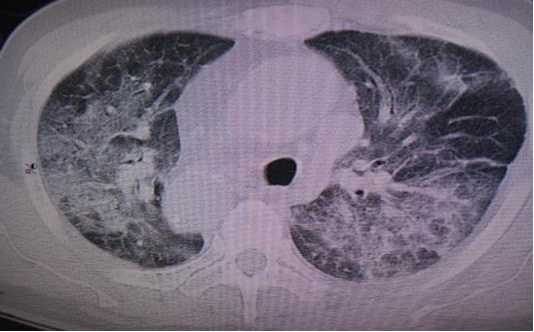

5.重症流感:流感病毒感染引起肺炎、发展为重症疾病[呼吸衰竭、急性呼吸窘迫综合征(acuterespiratory distress syndrome,ARDS)、感染性休克、心肌受累、中枢神经系统受累、多器官功能衰竭]或慢性基础疾病加重而需要住院治疗的患者。对于人感染新亚型流感(如尚未广泛传播,且致病性、病死率或重症风险尚未明确的甲型流感病毒亚型)的感染者,即使未完全符合上述重症流感的判定标准,也应被视为重症流感病例。